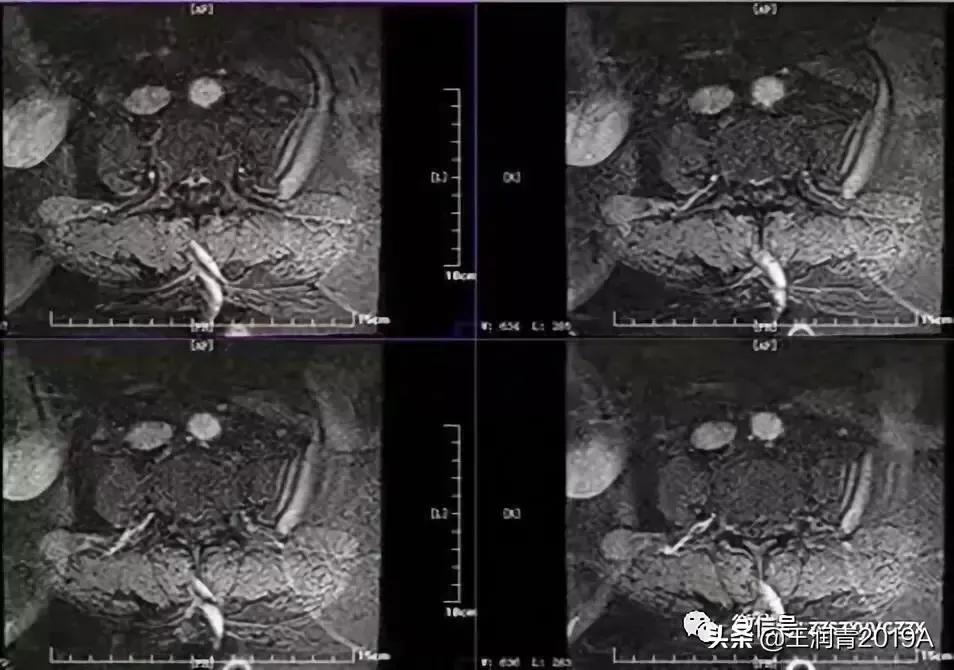

2、腰椎MR增强检查:平腰4椎体层面椎管内异常信号影,考虑腰椎间盘髓核脱出影(腰4-5)(图4-8)

5、定位:腰膨大及以下。双下肢麻木、无力、尿便*禁失**、下肢腱反射减弱,双足深浅感觉减退。定性:压迫?依据:中老年女性,既往有腰椎间盘手术史,此次急性起病,表现为双下肢麻木无力,尿便*禁失**症状,症状逐渐加重,结合临床及磁共振检查提示。

肌电图显示:双侧胫前肌及双侧腓肠肌内侧可见插入电位延长,静息状态可见纤颤、正锐波,募集反应减少提示神经源性损害,累及双侧,定位在根或脊髓前角,双侧股四头肌肌电图正常,排除L4,定位L5 S1 S2,四肢体感诱发电位:双上肢体感诱发电位正常,双下肢体感诱发电位外周段N9(腘窝记录)潜伏期正常,说明脊神经节后感觉纤维正常,皮层电位P40未引出,考虑脊神经节前或脊髓后索病变。

肌电图提示:腰骶神经根病变,累及L5 S1 S2脊髓节段

结合临床,患者有大小便*禁失**,考虑脊髓马尾综合征,多见于椎管狭窄。